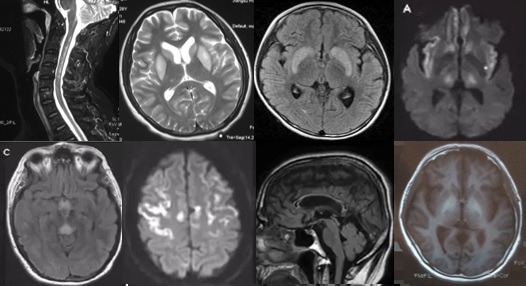

重要申明:以下每个部分会配磁共振图片,因疾病和影像之间存在同病异象、同像异病,为避免误导,图片不标注疾病,请各自鉴赏,另其中有部分图片来源于网络,有疑问可与本人联系。

一、M—metabolism代谢性

代谢性脑病的原因很多,包括氨基酸、有机酸、脂肪酸、糖等代谢异常,以及线粒体功能障碍等,导致高氨血症、低血糖、酸中毒和能量缺乏,引起脑功能障碍。我们在临床上看到的有缺血缺氧性脑病、低血糖致白质脑病、肝性脑病、肾性脑病、Wernicke脑病、线粒体脑病等。中枢神经系统受累的病灶在磁共振上可出现各种表现。